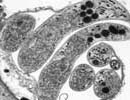

| Cryptosporidium hominis UKH5 |

|  Courtesy of Saul Tzipori, Tufts |

| Taxonomy: | Eukaryota | Alveolata | Apicomplexa | Conoidasida | Coccidia | Eucoccidiorida | Eimeriorina | Cryptosporidiidae | Cryptosporidium |  | Comment: | Cryptosporidium hominis is the dominant species which infects humans. Although generally self-limiting, this disease can cause fatalities in children and immunocompromised adults. The genome sequence of Cryptosporidium hominis shows features consistent with its life cycle as an obligate parasite. This organism lacks the genes necessary for the production of a number of biochemical building block such as nucleotides and amino acids. To compensate for this lack, the genome contains a large number of transporter or transporter-like genes. |  |  |  |   | Go to NCBI Taxonomy (237895) |